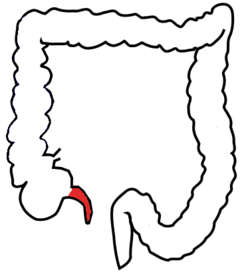

Anal Canal

Anus

Ascending/transverse/descending/sigmoid colon

Cecum

Haustra

Ileocecal valve

Ileum

Jejunum

Rectum

Taeniae coli

Vermiform appendix